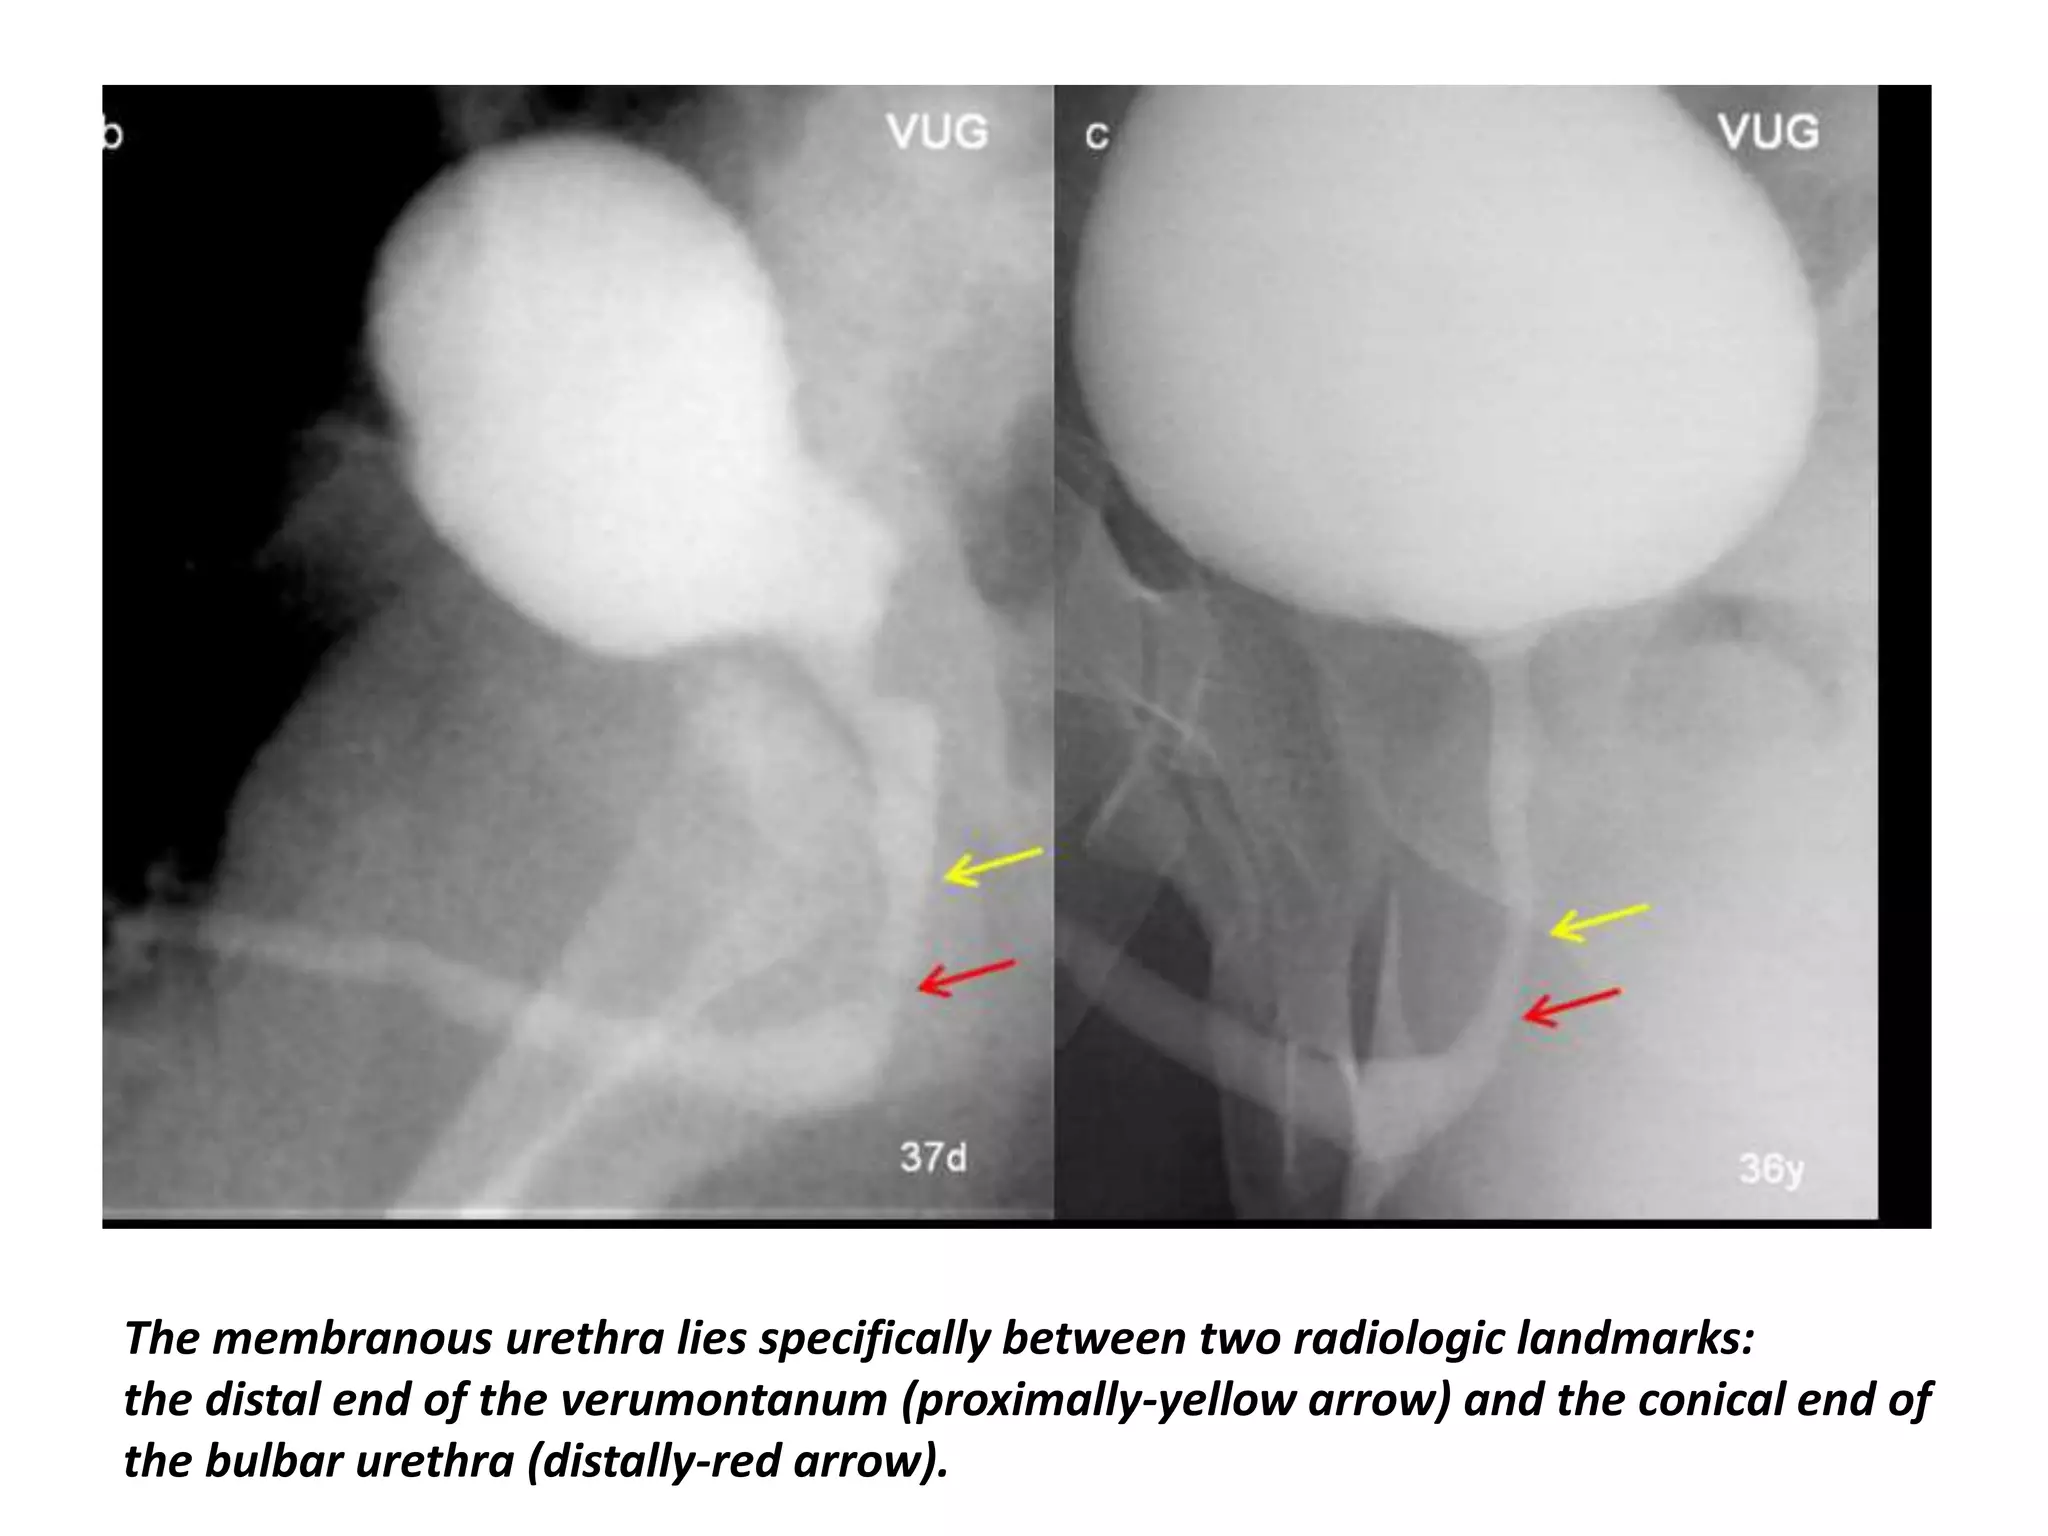

The membranous urethra lies specifically between two radiologic landmarks:

the distal end of the verumontanum (proximally-yellow arrow) and the conical end of

the bulbar urethra (distally-red arrow).